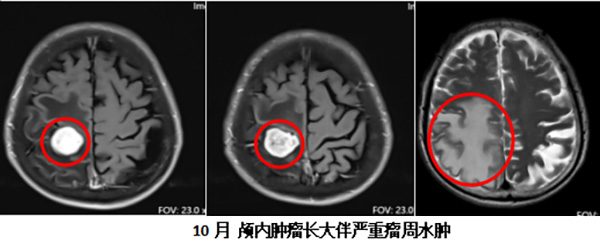

然而,疾病的进展不会因人们的主观回避而自动停止。到了10月份,老人开始出现左侧肢体活动不利,最初是有些笨拙,后来逐渐加重到下床费力。因为家属担心患者瘫痪以后没法照顾,焦急之中,他们来到了北京怀柔医院神经外科寻求帮助。

决策既定,手术团队制定了周详的手术计划。手术过程中,在术中超声辅助定位下,寻找到了中央后回受累最严重的狭小区域,经过最小化损伤通道,成功将位于功能区的肿瘤完整切除,并最大限度地保护了周边正常的神经组织。

手术效果立竿见影。术后,老人左侧肢体的肌力得到了明显改善,之前下床费力的症状基本完全缓解。这一成功的手术,不仅解决了最迫切的神经功能问题,极大地提升了患者的生存质量,也实现了团队的初步战略目标——为后续治疗打开了局面。